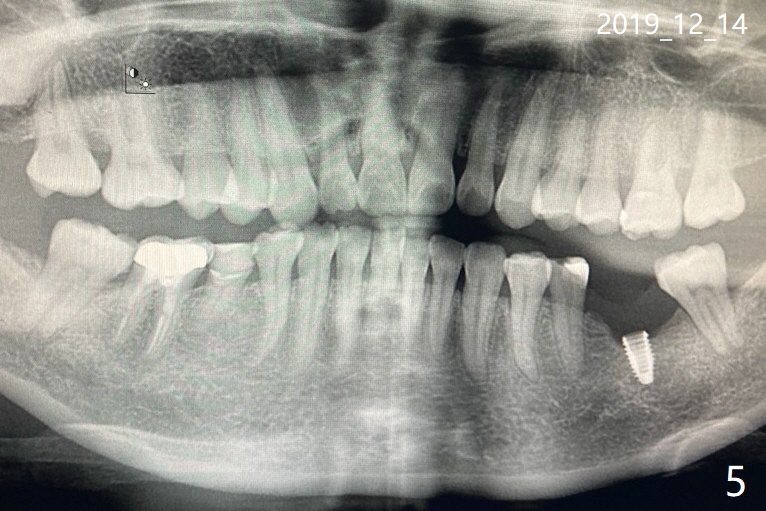

这边我找到有Neo种植体的诊所了,可那医生说应该植骨,重种。您能把我在美国时刚做完植体和装上牙冠后的x片发给我吗?我也把12月1号,8号和14号的x片发给您(图三至五). 另外,植体里的螺丝会磨没了吗? December 14, 2019, 3:21:23 AM EST

丽霞: 植体里的螺丝磨损很难证实,而基牙磨损容易看清楚。你术前骨头宽度还可以,高度差一些,要增加后者,医生技术要非常好。如果基牙有明显磨损,最好放置新的基牙,torque到30Ncm后,拍根尖片,证实基牙完全坐落在植体上,然后口内取模,即再也不要把基牙取出。最好在放入新的基牙前,放置healing abutment,让软组织不会阻碍基牙入位。

你的植体是用导航植入,应该位置正确,种植前考虑到第二磨牙需要往后面移位。如果医生认为需要取出植体,最好植入软组织水平植体,或者不容易松动骨组织水平植体,即植体与基牙之间连接比较稳当。虽然Neo种植牙好像在你身上容易松动,如果换了一种不容易松动的种类,由于你的咬合力大,你可能会把植体咬松,脱落。新的牙冠放入后,必须好好调整咬合。在发根尖片时,发现你应该做左下五,甚至左下七牙冠,可能让植体压力小些,基牙螺丝就不容易松动。祝你顺利